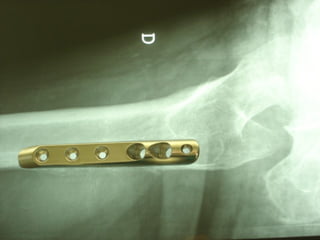

INDICAZIONI COMUNI Fratture sovracondiloidee Fratture intercondiliodee Fratture diafisarie distali PARTICOLARI Fratture con grave osteoporosi Fratture periprotesiche

VANTAGGI CHIRURGIA MININVASIVA Mini Open Inserimento della placca sottocutaneo per scivolamento Viti percutanee Preservazione dei tessuti molli Ridotto danno vascolare Rapida ripresa funzionale

LISS  NCB

NCB